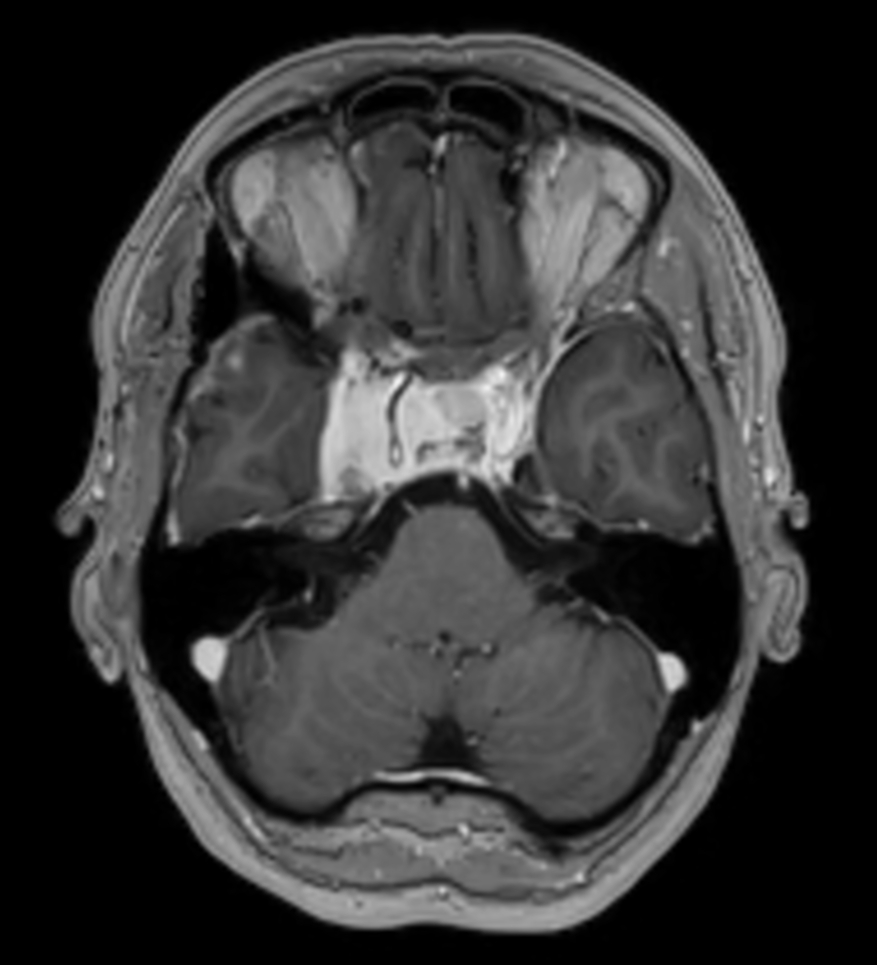

Young female referred for stereotactic treatment underwent MRI simulation.  Flex L Coils in combination with integrated FlexCoverage Posterior coil were used to image the patient in the stereotactic mask in Ingenia MR-RT 1.5T.

Axial T2w TSE post contrast